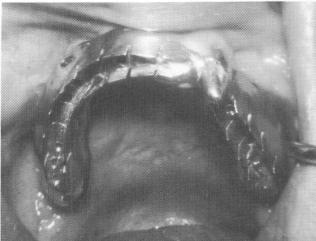

Fig. 10-203. Occlusion on both sides of the arch was can fully balanced.

then fastened to the mesostructure with the obliquely directed set screws. The bite was once again balanced (Fig. 10-203), and a postoperative radio-graph of the implants was taken (Fig. 10-204).